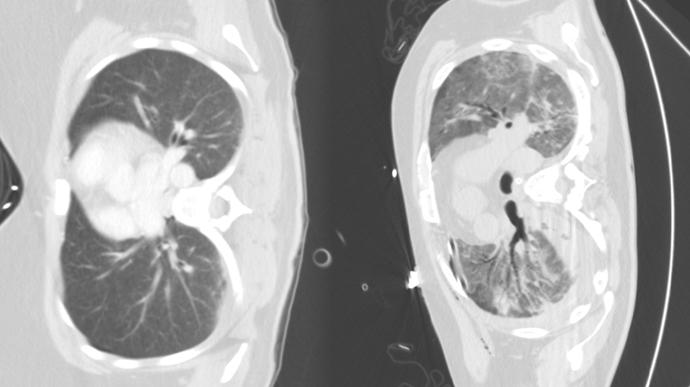

plíce

Foto k tématu plíce – stránka 2

plíce – nejnovější zprávy a fotografie plíce